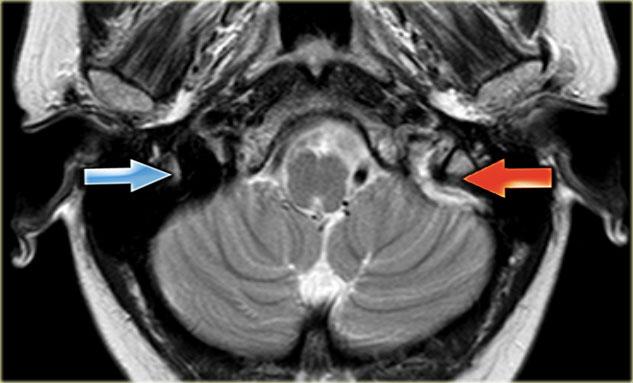

Mất tín hiệu trống dòng chảy bình thường trên MRI

Trên các chuỗi xung spin-echo, các tĩnh mạch não thông thoáng thường biểu hiện giảm tín hiệu do hiện tượng trống dòng chảy (flow void).

Tín hiệu trống dòng chảy thấy rõ nhất trên chuỗi xung T2W và FLAIR, nhưng đôi khi cũng có thể thấy trên chuỗi xung T1W.

Huyết khối sẽ biểu hiện bằng sự vắng mặt của tín hiệu trống dòng chảy.

Mặc dù đây không phải là dấu hiệu hoàn toàn đáng tin cậy, nhưng thường là một trong những dấu hiệu đầu tiên khiến ta nghĩ đến khả năng huyết khối tĩnh mạch.

Bước tiếp theo cần thực hiện là chụp có tiêm thuốc tương phản từ.

Hình ảnh bên trái là chuỗi xung T2W với tín hiệu trống dòng chảy bình thường ở xoang sigma phải và tĩnh mạch cảnh trong phải (mũi tên xanh dương).

Bên trái có tín hiệu cao bất thường là kết quả của huyết khối (mũi tên đỏ).